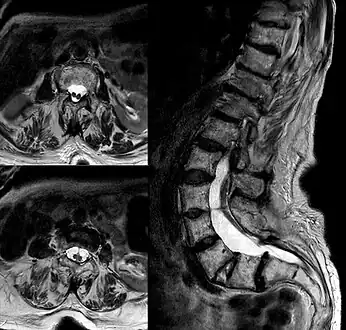

Diastematomyelia is a congenital disorder in which a part of the spinal cord is split, usually at the level of the upper lumbar vertebra in the longitudinal (sagittal) direction. This condition occurs in the presence of an osseous, cartilaginous or fibrous septum in the central portion of the spinal canal which then produces a complete or incomplete sagittal division of the spinal cord into two hemicords. When the split does not reunite distally to the spur, the condition is referred to as diplomyelia, which is true duplication of the spinal cord.

Diastematomyelia usually occurs between 9th thoracic and 1st sacral levels of the spinal column with most being at the level of the upper lumbar vertebra. Cervical diastematomyelia is a very rare entity. The extent (or length of spinal cord involved) varies from one affected individual to another. In approximately 60% of patients with diastematomyelia, the two hemicords, each covered by an intact layer of pia arachnoid, travel through a single subarachnoid space surrounded by a single dural sac. Each hemicord has its own anterior spinal artery. This form of diastematomyelia is not accompanied by any bony spur or fibrous band and is rarely symptomatic unless hydromyelia or tethering is present. The other 40% of patients have a bony spur or a fibrous band that passes through the two hemicords. In these cases, the dura and arachnoid are split into two separate dural and arachnoidal sacs, each surrounding the corresponding hemicord which are not necessarily symmetric. Each hemicord contains a central canal, one dorsal horn (giving rise to a dorsal nerve root), and one ventral horn (giving rise to a ventral nerve root.) One study showed the bony spur typically situated at the most inferior aspect of the dural cleft. They advised that if the imaging appears to show otherwise, a second spur (present in about 5% of patients with diastematomyelia) is likely to be present.

Adult presentation in diastematomyelia is unusual. With modern imaging techniques, various types of spinal dysraphism are being diagnosed in adults with increasing frequency. The commonest location of the lesion is at first to third lumbar vertebrae. Lumbosacral adult diastematomyelia is even rarer. Bony malformations and dysplasias are generally recognized on plain x-rays. MRI scanning is often the first choice of screening and diagnosis. MRI generally give adequate analysis of the spinal cord deformities although it has some limitations in giving detailed bone anatomy. Combined myelographic and post-myelographic CT scan is the most effective diagnostic tool in demonstrating the detailed bone, intradural and extradural pathological anatomy of the affected and adjacent spinal canal levels and of the bony spur.